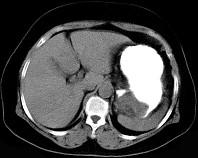

女43岁上腹不适多年,体检行CT扫描如图,最可能的诊断为 ( )A.胃癌B.胃平滑肌瘤C.胃平滑肌肉瘤D.胃淋巴瘤E.胃蛔虫团块

问题 女43岁上腹不适多年,体检行CT扫描如图,最可能的诊断为 ( )

选项 A.胃癌 B.胃平滑肌瘤 C.胃平滑肌肉瘤 D.胃淋巴瘤 E.胃蛔虫团块

答案 B